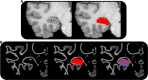

The hippocampus supports multiple cognitive functions including episodic memory. Recent work has highlighted functional differences along the anterior-posterior axis of the human hippocampus, but the neuroanatomical underpinnings of these differences remain unclear. We leveraged track-density imaging to systematically examine anatomical connectivity between the cortical mantle and the anterior-posterior axis of thein vivo human hippocampus. We first identified the most highly connected cortical areas and detailed the degree to which they preferentially connect along the anterior-posterior axis of the hippocampus. Then, using a tractography pipeline specifically tailored to measure the location and density of streamline endpoints within the hippocampus, we characterised where these cortical areas preferentially connect within the hippocampus. Our results provide new and detailed insights into how specific regions along the anterior-posterior axis of the hippocampus are associated with different cortical inputs/outputs and provide evidence that both gradients and circumscribed areas of dense extrinsic anatomical connectivity exist within the human hippocampus. These findings inform conceptual debates in the field and emphasise the importance of considering the hippocampus as a heterogeneous structure. Overall, our results represent a major advance in our ability to map the anatomical connectivity of the human hippocampusin vivo and inform our understanding of the neural architecture of hippocampal-dependent memory systems in the human brain.

The brain allows us to perceive and interact with our environment and to create and recall memories about our day-to-day lives. A sea-horse shaped structure in the brain, called the hippocampus, is critical for translating our perceptions into memories, and it does so in coordination with other brain regions. For example, different regions of the cerebral cortex (the outer layer of the brain) support different aspects of cognition, and pathways of information flow between the cerebral cortex and hippocampus underpin the healthy functioning of memory. Decades of research conducted into the brains of non-human primates show that specific regions of the cerebral cortex anatomically connect with different parts of the hippocampus to support this information flow. These insights form the foundation for existing theoretical models of how networks of neurons in the hippocampus and the cerebral cortex are connected. However, the human cerebral cortex has greatly expanded during our evolution, meaning that patterns of connectivity in the human brain may diverge from those in the brains of non-human primates. Deciphering human brain circuits in greater detail is crucial if we are to gain a better understanding of the structure and operation of the healthy human brain. However, obtaining comprehensive maps of anatomical connections between the hippocampus and cerebral cortex has been hampered by technical limitations. For example, magnetic resonance imaging (MRI), an approach that can be used to study the living human brain, suffers from insufficient image resolution. To overcome these issues, Dalton et al. used an imaging technique called diffusion weighted imaging which is used to study white matter pathways in the brain. They developed a tailored approach to create high-resolution maps showing how the hippocampus anatomically connects with the cerebral cortex in the healthy human brain. Dalton et al. produced detailed maps illustrating which areas of the cerebral cortex have high anatomical connectivity with the hippocampus and how different parts of the hippocampus preferentially connect to different neural circuits in the cortex. For example, the experiments demonstrate that highly connected areas in a cortical region called the temporal cortex connect to very specific, circumscribed regions within the hippocampus. These findings suggest that the hippocampus may consist of different neural circuits, each preferentially linked to defined areas of the cortex which are, in turn, associated with specific aspects of cognition. These observations further our knowledge of hippocampal-dependant memory circuits in the human brain and provide a foundation for the study of memory decline in aging and neurodegenerative diseases.